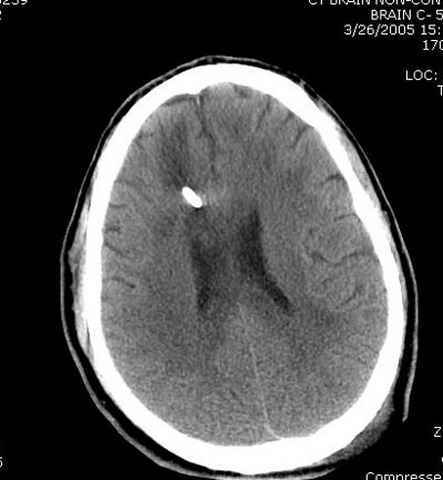

Наблюдается службой травмы и нейрохирургии (ICP) Increased Intracranial Pressure by ventricular cateter

монииторинг

-Согласен, рана до прихода пластического хирурга была 38х13 см, можно было постараться закрыть сверху, а в нижнем отделе где был ожог, применить кожную пластику меньшим размером. К моему удивлению и разочарованию, когда вернулся из другой операционной (шли пареллельные операции), он уже успешно заканчивал свое дело. Кстати недавно разговаривал с нейрохирургом, он снял ICP (intracranial prеssure monitor), внутричерепное давление стабилизировалось, ортопеды и хирурги закончили с лечением, теперь длительное неврологическое восстановление.